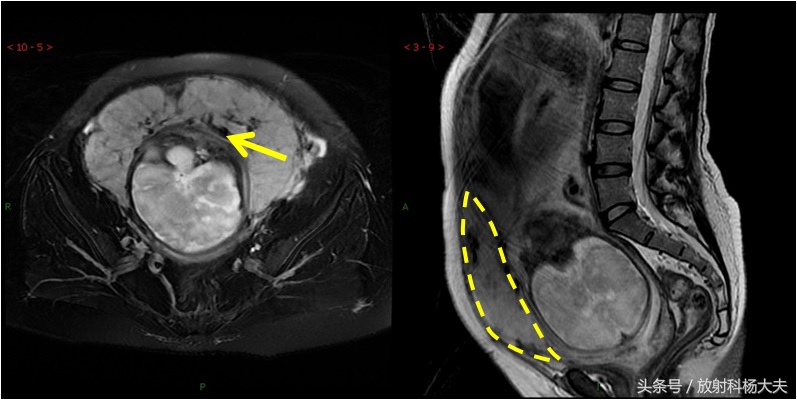

在MRI上显示植入部位子宫肌层局部均不同程度地变薄,胎盘基底面不规则。低信号的子宫肌层内见局部高信号病灶,呈结节状或三角形、锯齿状、不规则形,T2WI胎盘内信号不均匀,内可见较多、粗大的流空血管影和低信号带。严重时胎盘可穿过肌层,穿通部位肌层信号中断,胎盘基底面与子宫壁融合,分界不清。但请关注,目前的技术,MRI的诊断准确率也只能做到82%而已。

胎盘植入的MRI图。黄箭所示黑黑的东西就是一些粗大的血管,可以想象这些血管破裂会有多可怕的后果。另外出血的原因是胎盘植入到子宫壁内,难以剥离。